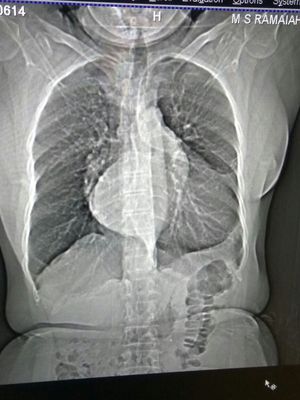

Dx?